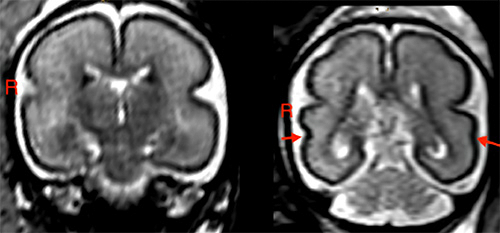

Researchers found that even low amounts of alcohol consumption in pregnant women can lead to early and diffuse structural changes in brain regions related to key functions including language development.